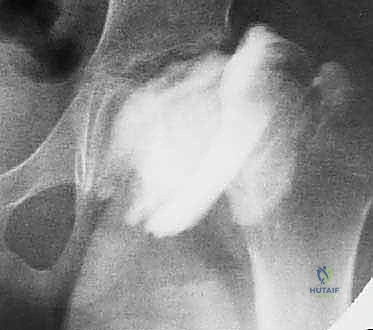

- الأشعة السينية الديناميكية (Dynamic X-rays): يتم أخذ صور بأوضاع مختلفة (فتح الساق وضمها) لمراقبة كيفية تحرك رأس الفخذ داخل التجويف، وتأكيد وجود انحراف المفصل (Hinge Abduction).

- تصوير المفصل الظليلي (Arthrography): إجراء حيوي يتم فيه حقن صبغة داخل المفصل تحت التخدير أو التهدئة، وتصوير المفصل بالأشعة الحية (Fluoroscopy). هذا الفحص هو المعيار الذهبي لتأكيد الاصطدام وتحديد زاوية القطع المثالية التي ستلغي هذا الاصطدام.